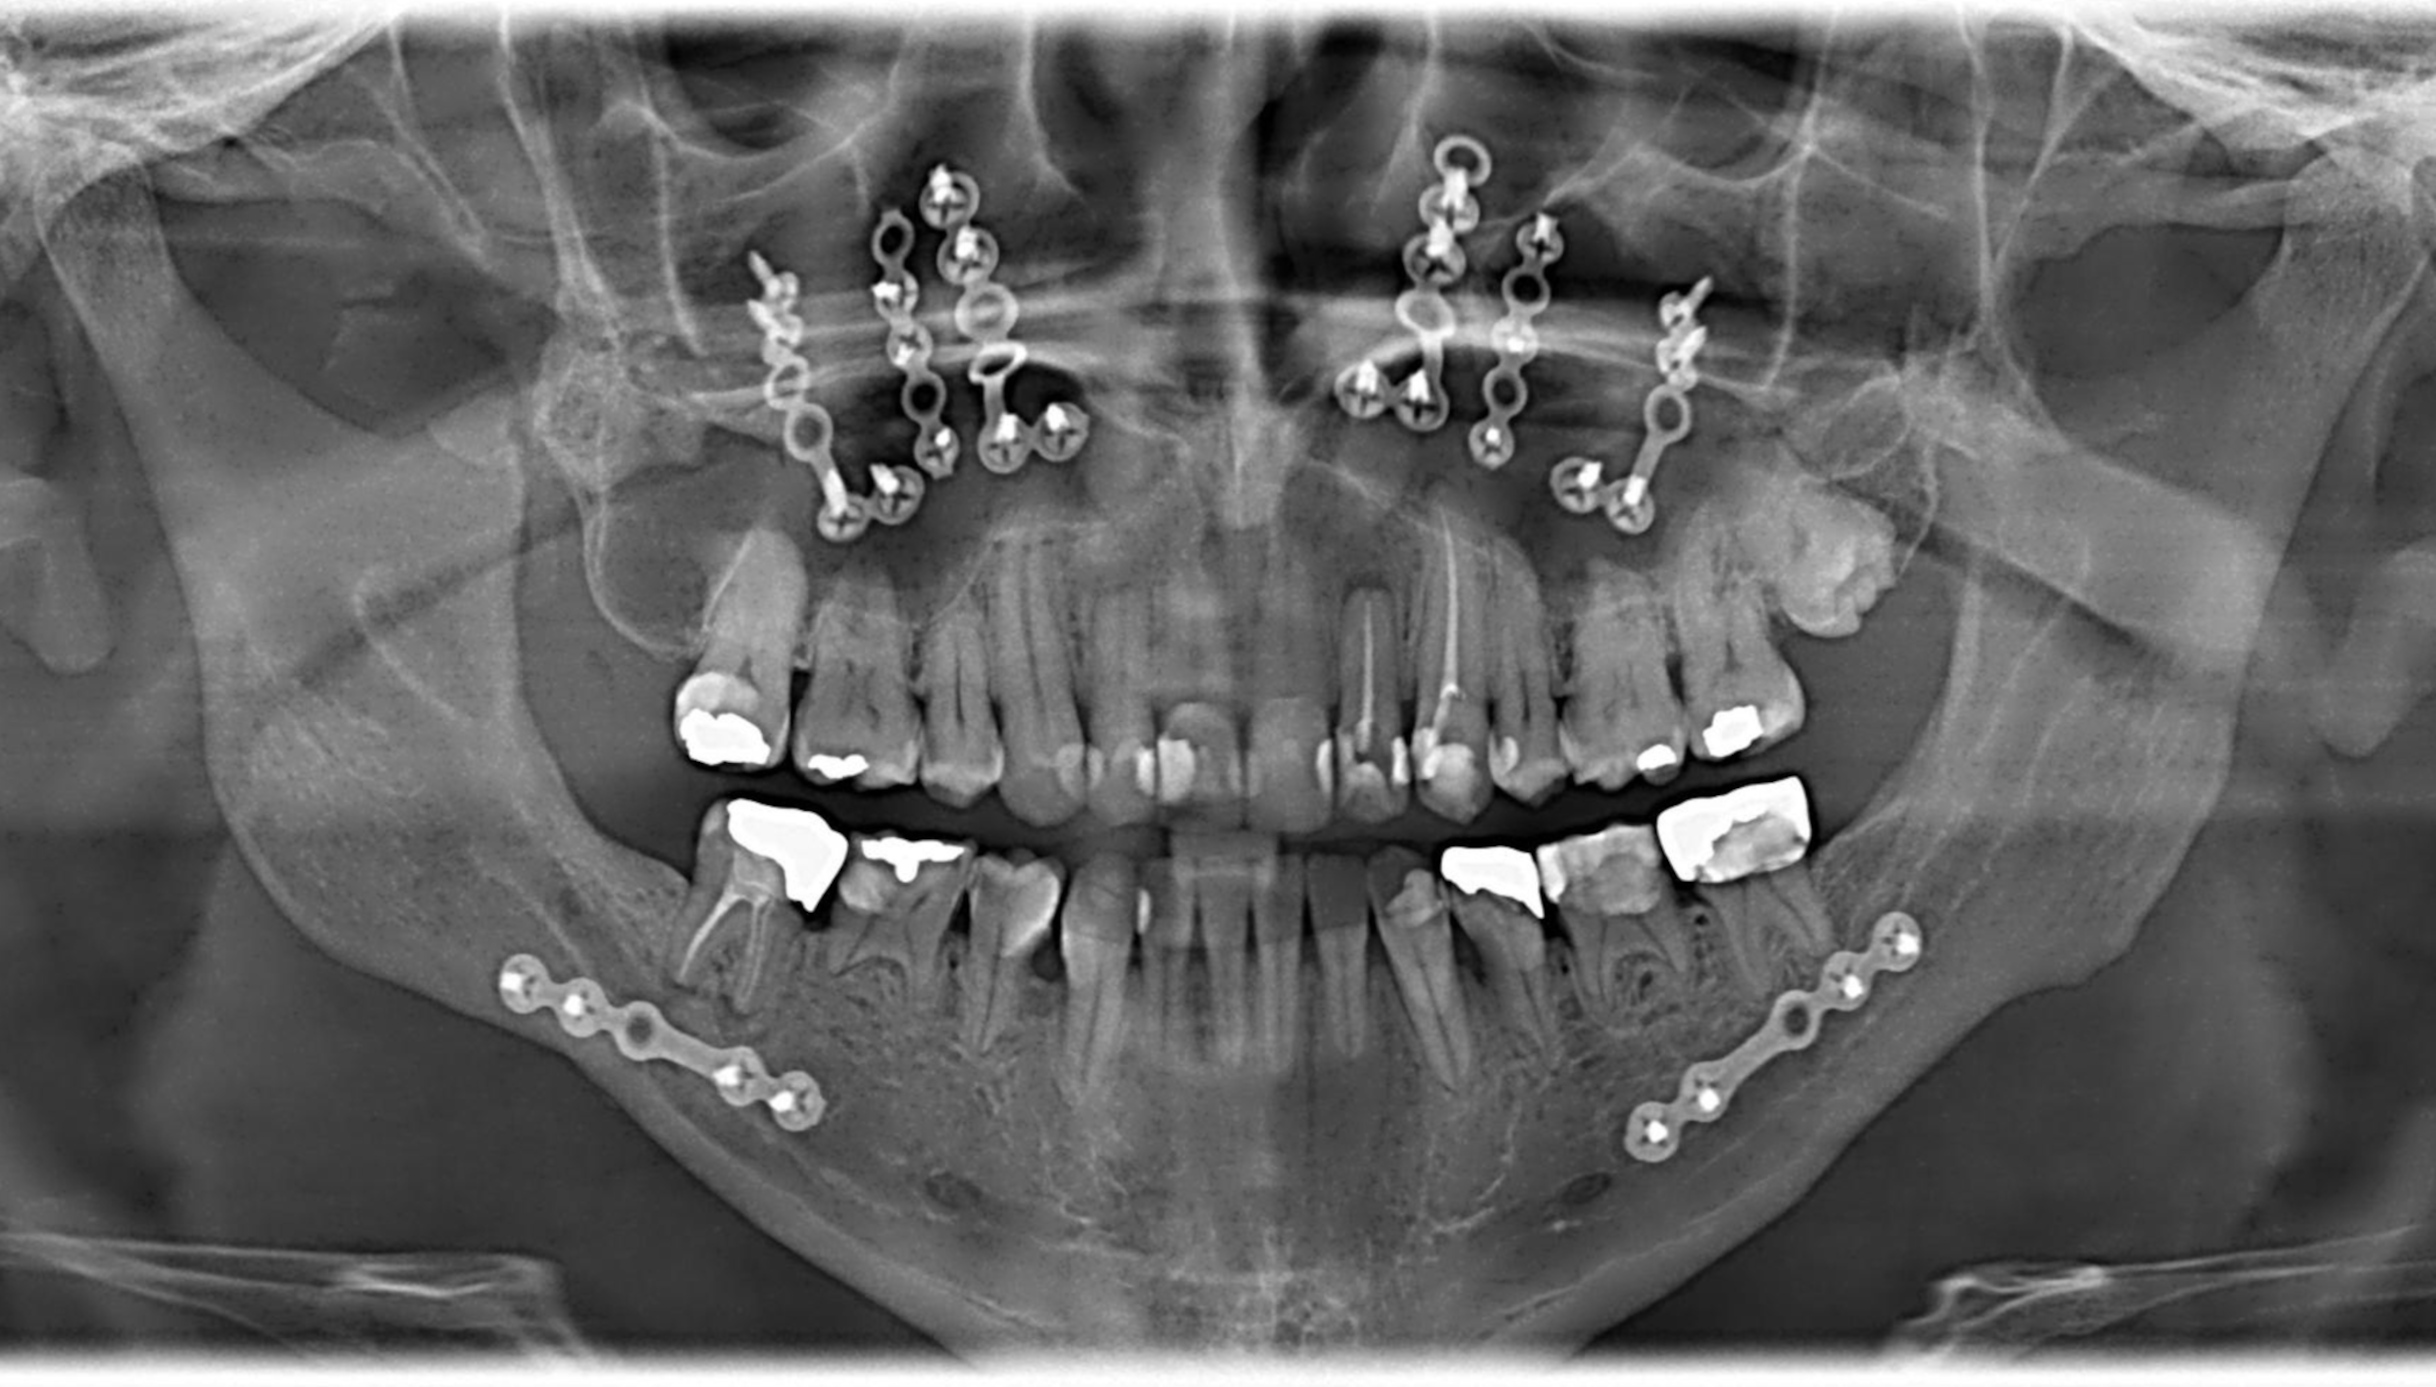

Процедура видалення кіст

Ви думаєте, просто пішов, видалив і все? А тут цілий процес: анестезія, вирізання, залікування. І це ще не все…

- Спочатку роблять місцеву анестезію. Нікому не хочеться відчувати біль.

- Потім – акуратна резекція кісти. Це, знаєте, таки мистецтво.

- І вже далі – шви, обробка, контроль болю.